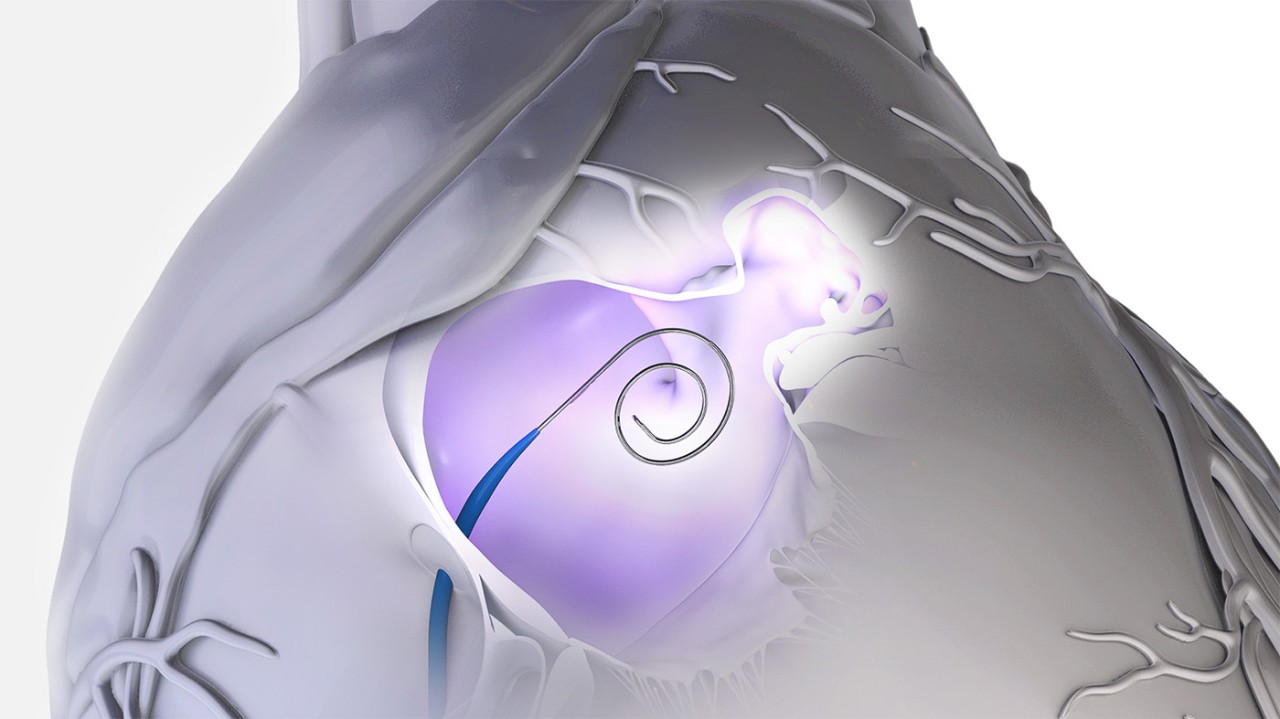

Access LA with precision

Precision radiofrequency (RF) puncture technology to optimize transseptal location for any anatomy

Secure effortless delivery

Instantly gain and maintain access without exchanges